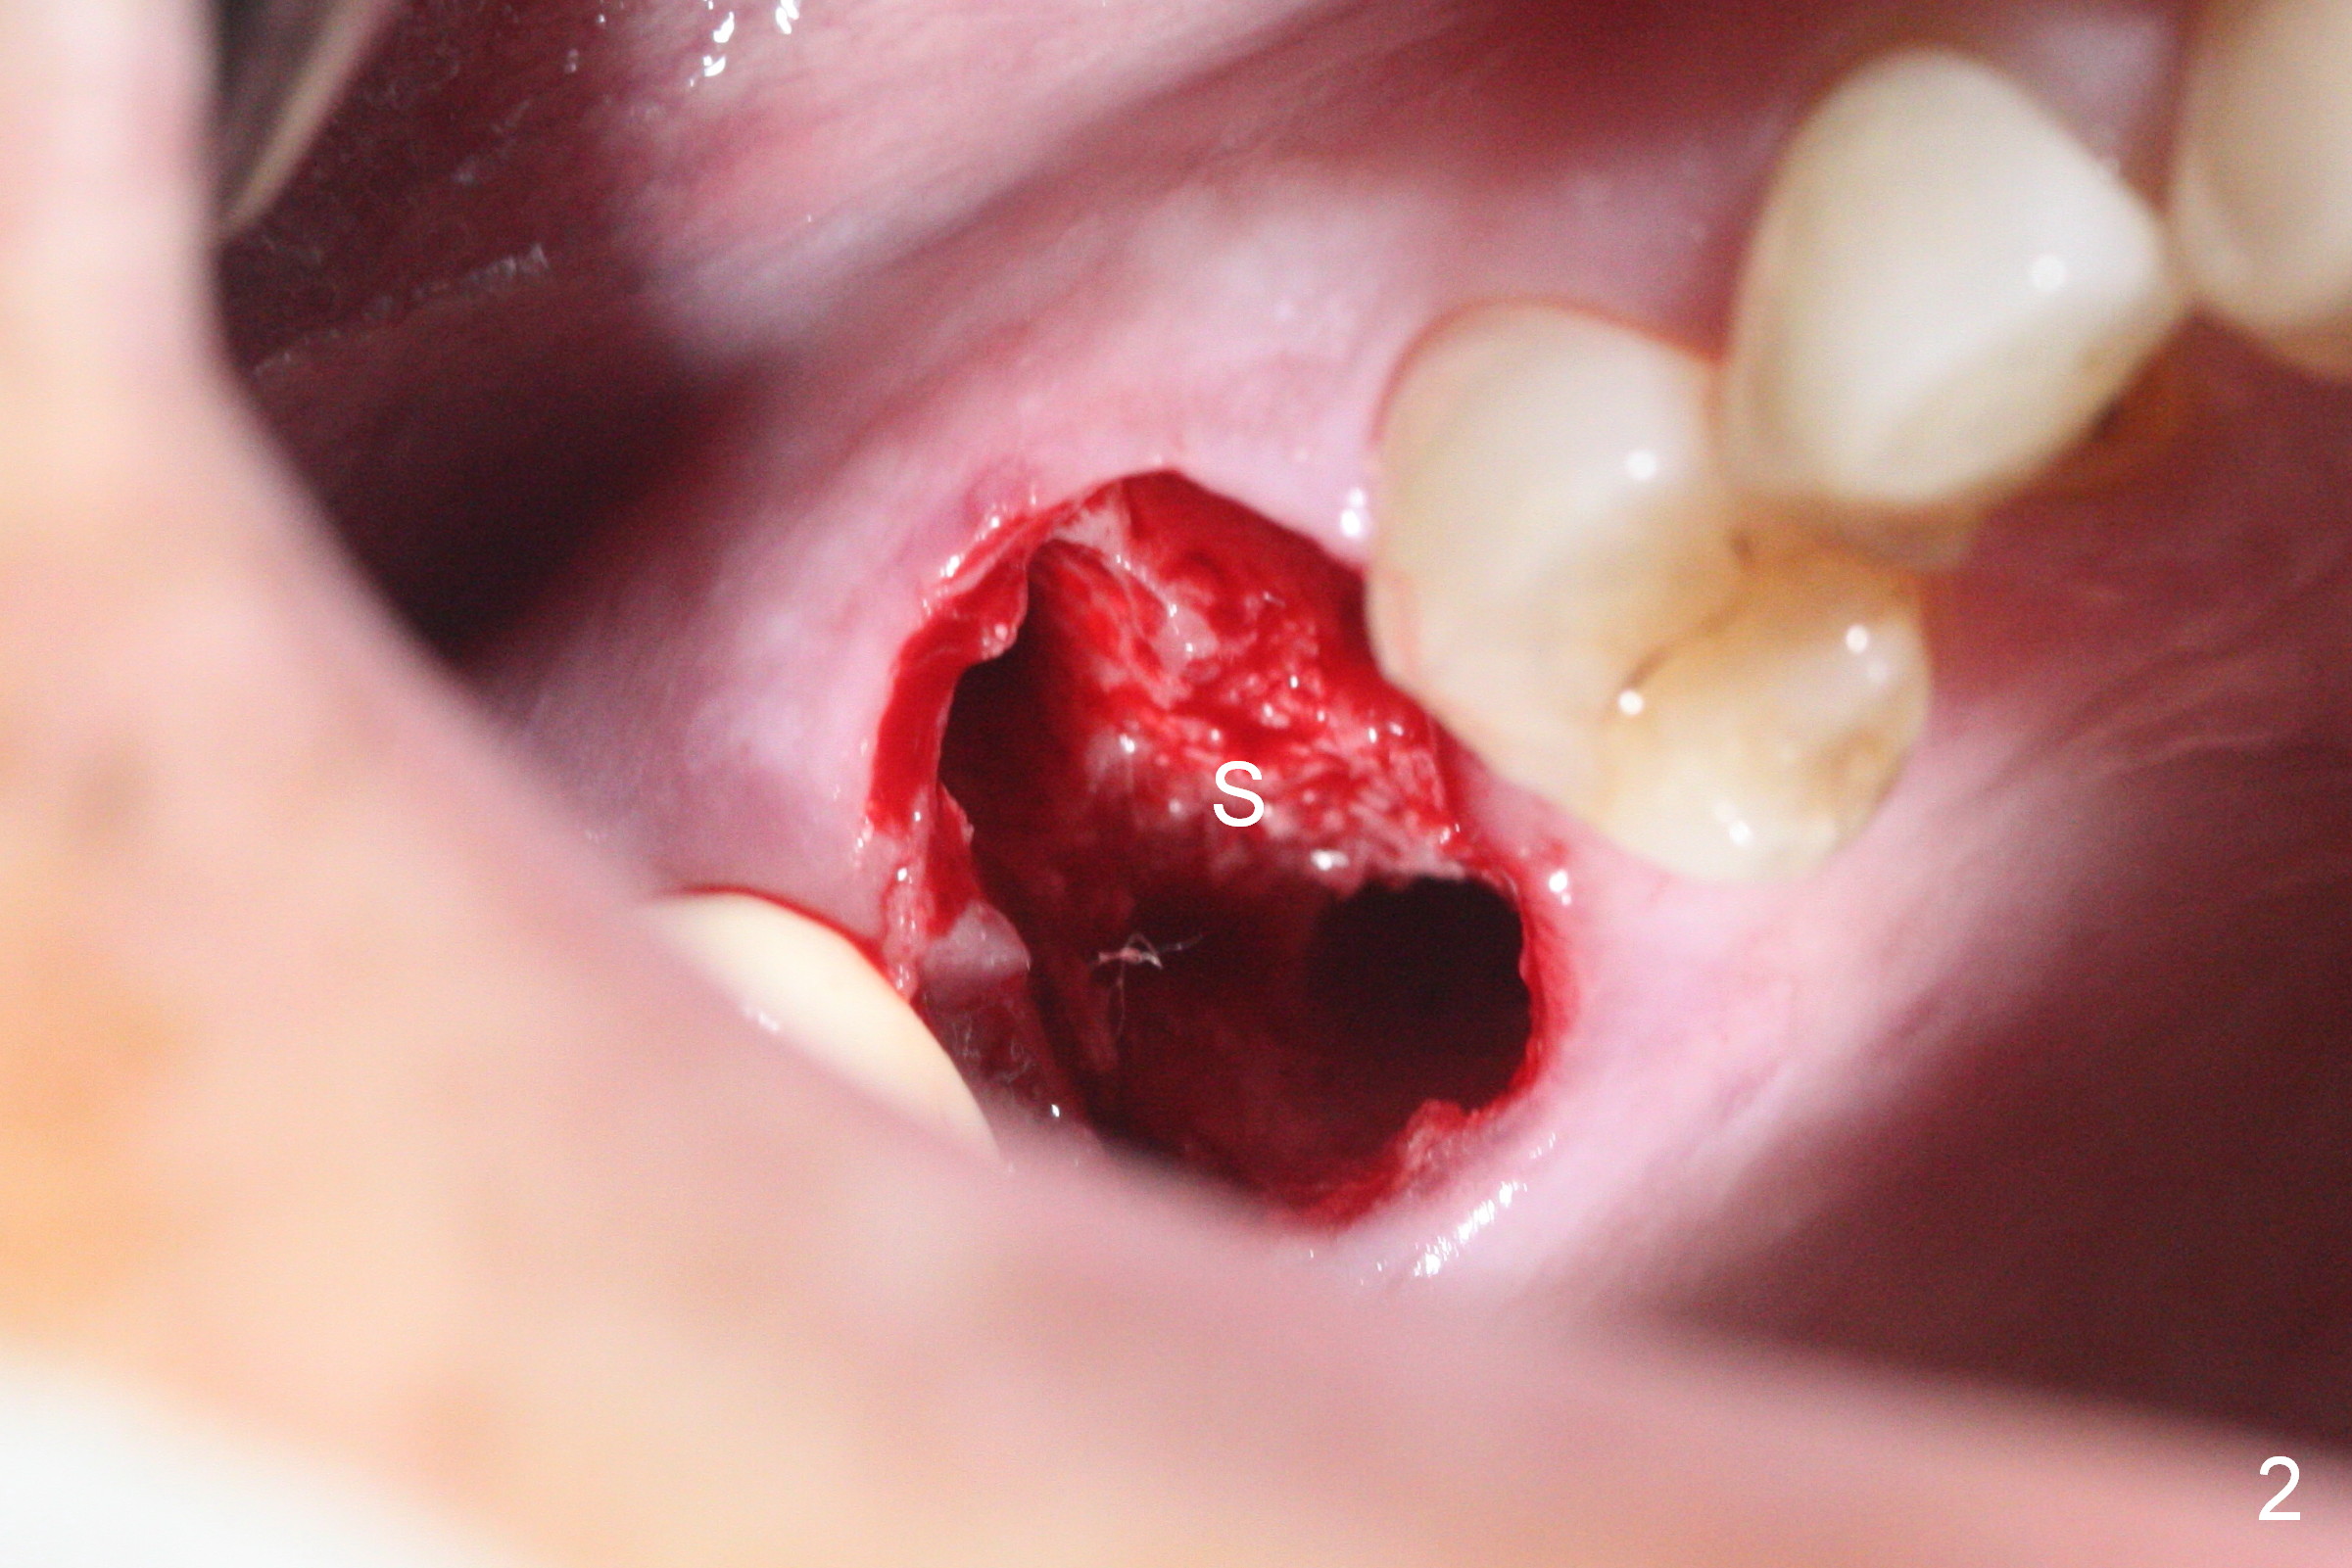

The patient returns with chief complaint of crown is loose with pain 3 months postop (Fig.7). Under local anesthesia, the provisional is removed. The gingiva is erythematous. The implant has mobility. A healing abutment is placed (6x2 mm). One month later, the implant remains unstable. The patient is scheduled to return 3.5 months postop to either retighten the implant with healing screw or replace with a 6x17 mm Tatum implant (Fig.9) after changing trajectory (Fig.8 red arrow).